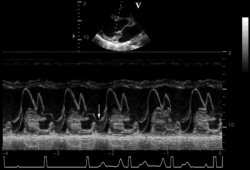

May result from abnormal elasticity with redundancy and enlargement of various portions of the mitral valvular apparatus, including the mitral annulus, chordae tendineae, and leaflets.[5][6][7][Figure caption and citation for the preceding image starts]: Posterior mitral valve prolapse on M-mode echoFrom the collection of Samir Kapadia and Mehdi H. Shishehbor [Citation ends].

[Figure caption and citation for the preceding image starts]: Parasternal long-axis view showing posterior mitral leaflet prolapseFrom the collection of Samir Kapadia and Mehdi H. Shishehbor [Citation ends].